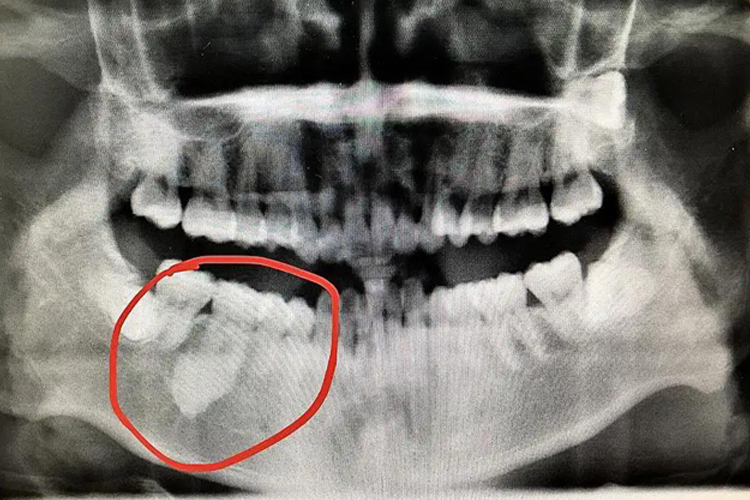

牙骨质瘤好发于下颌前牙、前磨牙区。肿瘤紧贴于牙根部,生长缓慢,一般无自觉症状,肿瘤压迫神经可引起疼痛。有时是在影像学检查才发现本病,X线片显示根尖周围有不透光阴影。